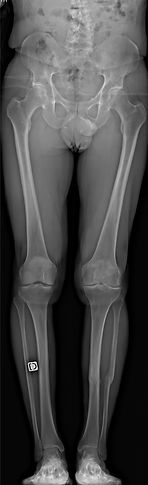

Une PANGONOMETRIE : c'est une radiographie de l'ensemble de vos deux membres inférieurs qui permettra de mesurer la déformation de votre genou pour pouvoir la corriger

Pangonométrie